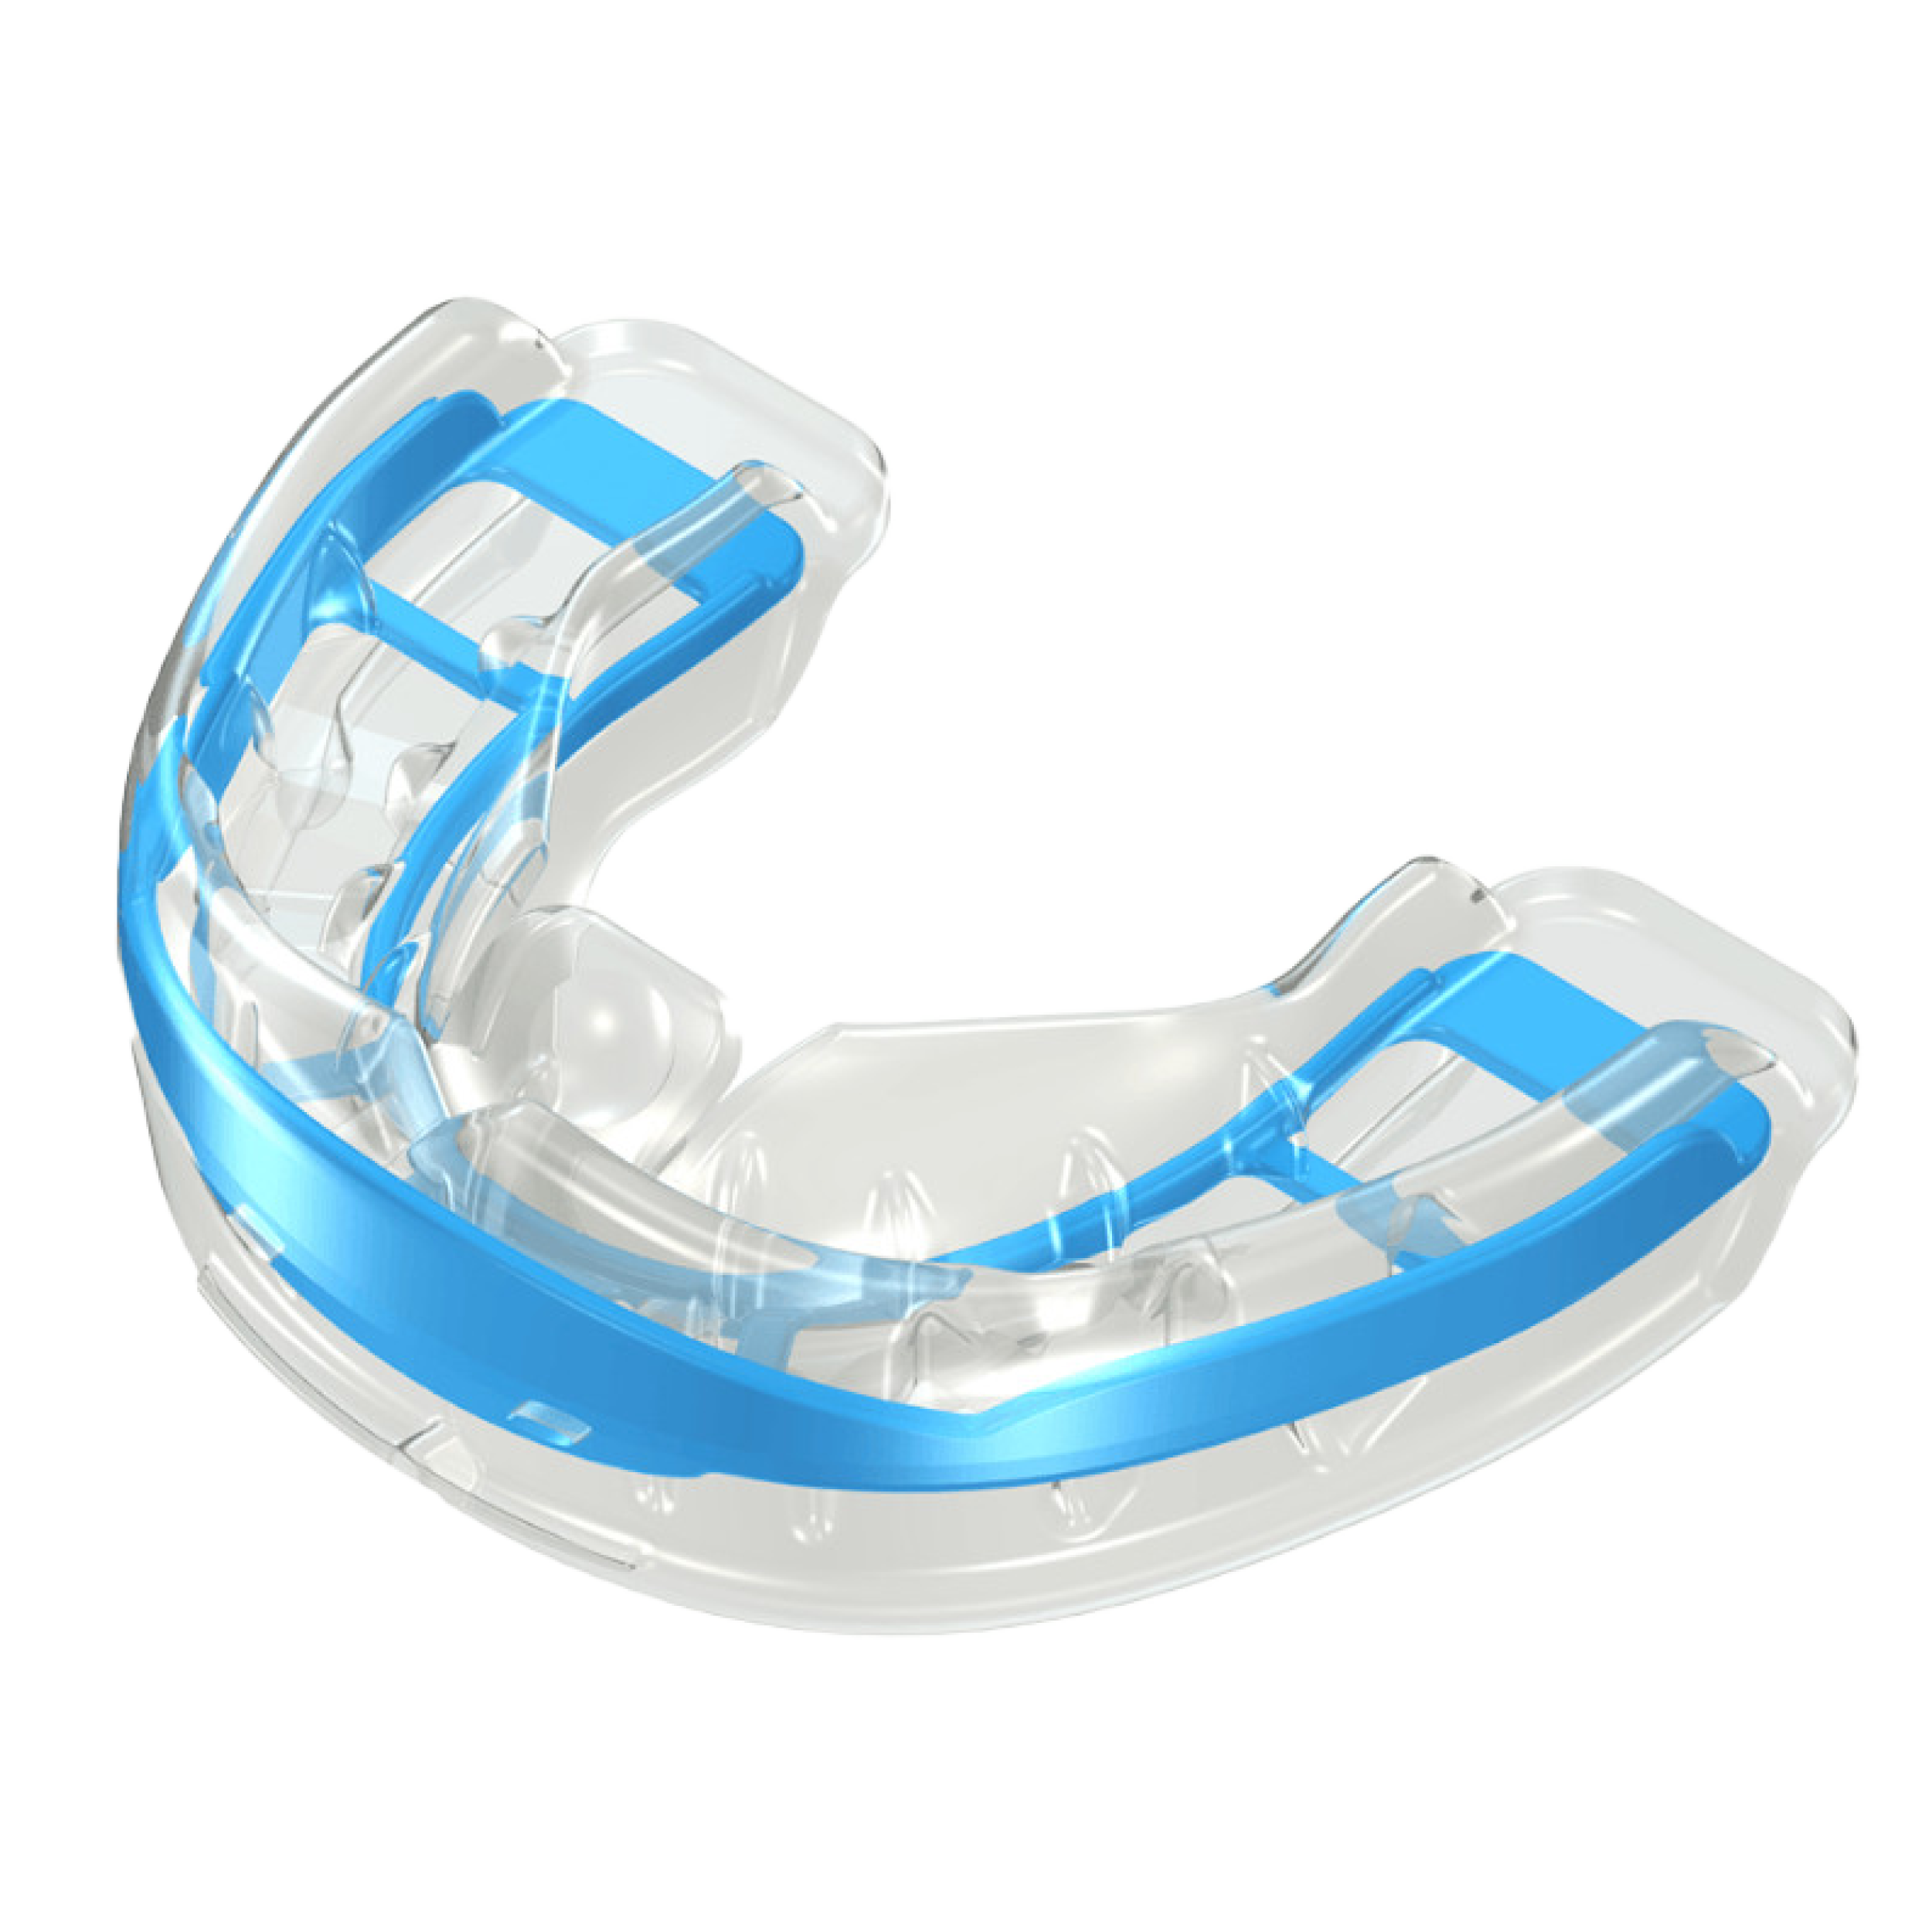

Myobrace®

La tecnología australiana avanzada que trata la fuente de problemas problemas Miofuncionales

Aparato + Ejercicio =

Receta perfecta

Myobrace for Juniors y Myobrace for Kids for children trabajan en la causa del problema corrigiendo la causa de los dientes torcidos tan pronto como estos problemas se hacen evidentes y mientras la adaptabilidad biológica de los niños está en su punto máximo.

Mejorar estos malos hábitos miofuncionales durante la infancia permitirá al niño tener una alineación natural de los dientes y mejorar el desarrollo de la mandíbula..

Myobrace® for Teens es un sistema de Odontología Miofuncional con el objetivo principal de corregir la respiración bucal y los hábitos miofuncionales incorrectos que causan maloclusión, y guía los dientes permanentes para que erupcionen en su alineación natural.

Myobrace® para adultos es un sistema para la dentición permanente.

Para el paciente adulto, todo el crecimiento ya se ha producido y los dientes están en su posición más estable. La respiración bucal y los hábitos incorrectos de deglución se han establecido durante muchos años y necesitan ejercicios miofuncionales para ser corregidos.